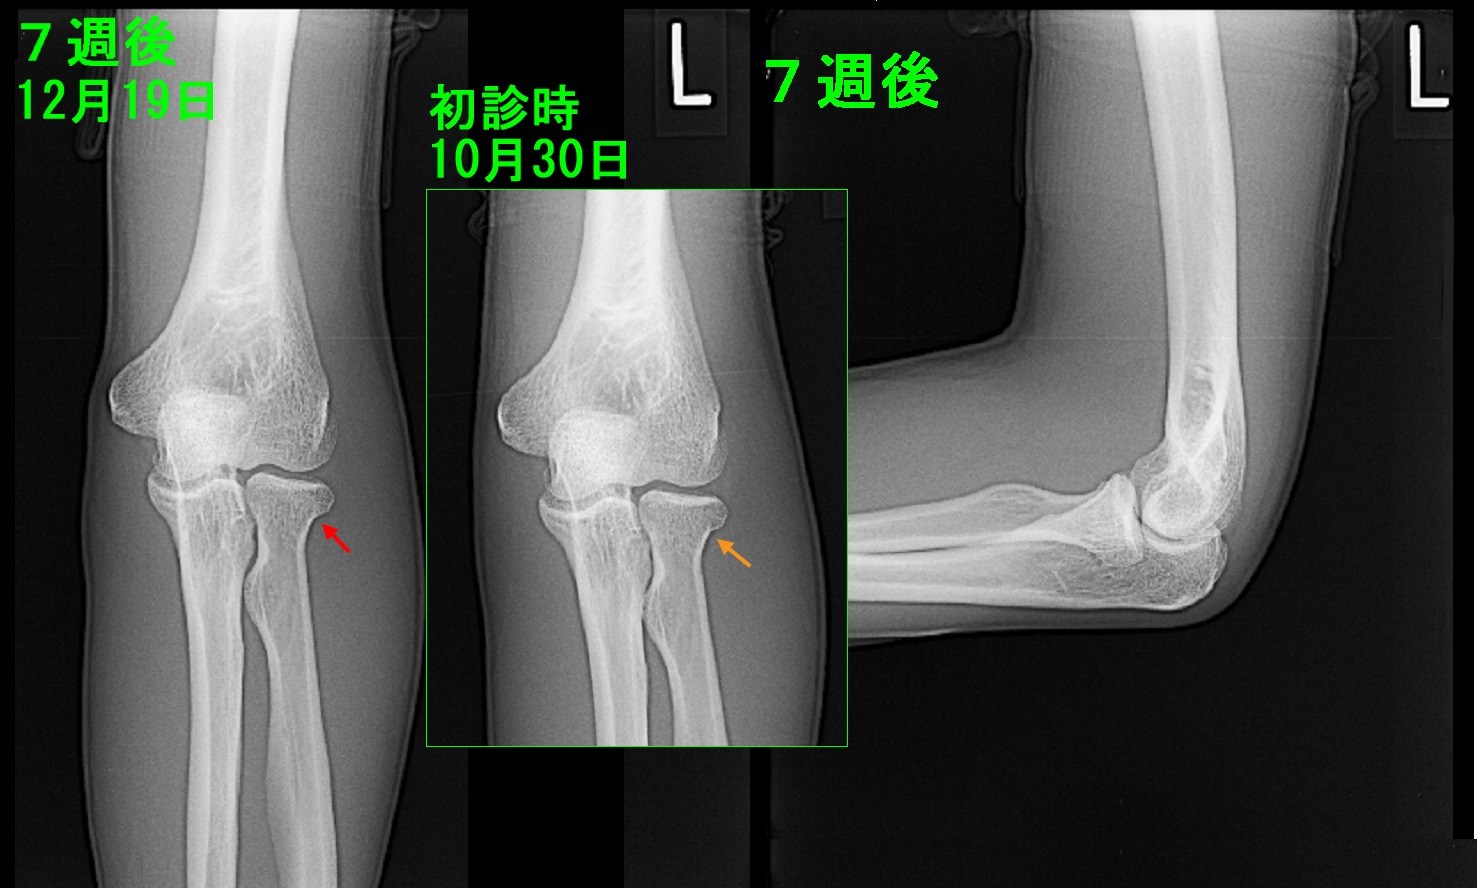

22才男 7週後Xp.jpg

12月19日受傷後7週のレントゲン像ですが、15才のバレーボール部員のような仮骨の形成の確認は困難です。折れてずれているような骨折でも7週経過すれば仮骨が形成されて日常生活には支障のないような強度に骨折は治癒することが通常です。元々レントゲン像では確認できないような軽微な骨折ですから、レントゲンで仮骨が確認されなくても十分骨折治癒は進んでいるはずです。私は普通に逮捕の訓練を再開しても良いと説明しました。以後、患者さんは受診されていません。